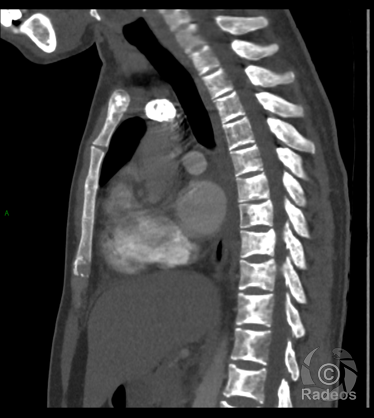

Aspect IRM d'une fibromatose profonde de la paroi abdominale. Découverte fortuite d'un angiome hépatique gauche.

Fibromatose profonde de type desmoïde